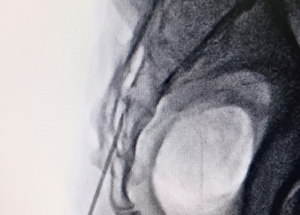

Expert spine services including minimally invasive surgery, pain management, and deformity correction.